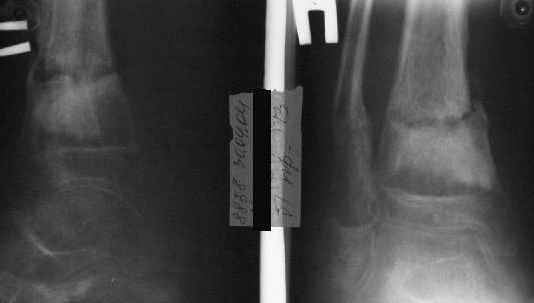

Ребенок 12 лет, поступил после падения с высоты примерно 2,5м.

Перелом костей н\3 правой голени со смещением. Перелом большеберцовой кости можно охарактеризовать как компрессионно-оскольчатый.

Скелетное вытяжение за пяточную кость.

В первые сутки значительный отек с\3, н\3голени, стопы с развитием практически неуловимого в нашей стране ;) компартмент синдрома (фасциотомии не проводилось), недочеты по укладке на скелетном

вытяжении.

Формирование некроза кожи по задней поверхности н\3 голени~ 1 %, вторичное заживление, кожная пластика. Нейропатия м\берцового нерва (отсутствие активного разгибания 1 пальца) На вытяжении около 8 нед, в дальнейшем в гипсовых повязках ~ 8 мес.

В январе 2005: варусная деформация н\3 голени, болевой с-м, комбинированная контрактура г\стопного сустава, нейропатия м\берцового нерва сохраняется слабость разгибания 1 пальца.

Операции: 1 Клиновидная резекция на вершине деформации м\берцовой кости.

2 Тугоподвижный ложный сустав н\3 б\берцовой кости. Рубцы выполняющие пространство между отломками, канал проксимального отломка иссечены.

Одномоментное устранение деформации, остеосинтез Г-образной пластиной.

Пластика по Хахутову.

Заживление проксимальной части раны вторичным натяжением без нагноения. Рана зажила. Спицы удалены через 1,5 недели после операции.

Так как речь зашла непосредственно о травме, см этапные

снимки. Как все было

Первичные

Вытяжение